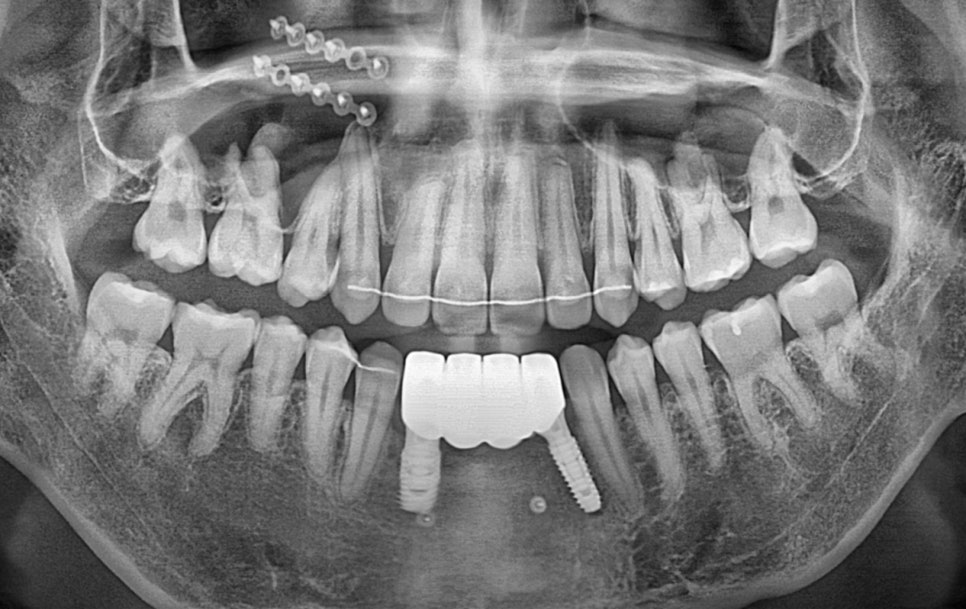

▲ 최종 완료 파노라마 사진

심을 잇몸뼈도 없었을뿐더러 양옆의 치아들도 예후가 좋지 않았기에

# 42 43 발치 이후에 이 치아들 쪽에 심고 브릿지로 연결하였습니다.

이 환자분은 원래도 앞니 쪽에 잇몸뼈가 부족한 상태였긴 했지만

교정 이후 치아의 이동으로 인해 잇몸이 약해서 더 퇴축되기도 했었습니다